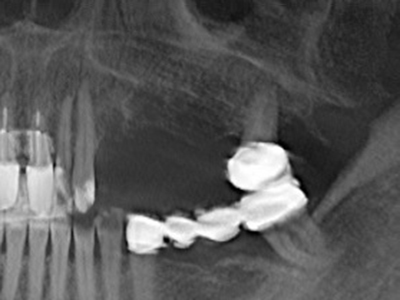

Aplicación: Preparación cerca del nervio

Como ya se ha mencionado, en el ámbito de la odontología conservadora también existen áreas en las que está indicada la cirugía piezoeléctrica. El uso de insertos de trabajo especiales facilita la representación del ápice radicular y, sobre todo en el área de los premolares inferiores y superiores, protege mejor los nervios y las mucosas del seno maxilar. En el caso de un cierre apical no estanco, los insertos de diamante acodados preparan de forma exacta y selectiva la cavidad de resección para el material de relleno retrógrado de la raíz. Gracias a la técnica de ultrasonidos, los insertos pueden presentar un diseño muy estilizado, lo que mejora la visión global y el tamaño de la cavidad de acceso. De este modo, en esta indicación, el uso de la cirugía por ultrasonidos se encuentra entre los métodos estándar para una apicectomía (Del Fabbro, Tsesis et al. 2010, Scarano, Artese et al. 2012).

Si es preciso realizar intervenciones quirúrgicas en las que el hueso está en contacto directo con estructuras sensibles, como son los vasos sanguíneos o los nervios, los instrumentos rotativos presentan un enorme potencial de provocar lesiones iatrogénicas. Así, precisamente en la representación de nervios después de una lesión iatrogénica, o en el transcurso de la lateralización de un nervio para resecciones, reconstrucciones o incorporación de implantes, los equipos piezoeléctricos pueden resultar muy útiles para preparar la tapa ósea y retirar las partes de tejido duro cercanas al nervio (fig. 17-20). Por lo general, un ligero contacto del cordón nervioso con el inserto piezoeléctrico no tiene consecuencia alguna; ahora bien, un procedimiento poco cuidadoso con movimientos tipo sierra o piezas de trabajo sobre la base ósea aún existente puede provocar lesiones nerviosas temporales o incluso permanentes. Con todo, el riesgo de sufrir una lesión de este tipo se considera significativamente inferior que en los casos en los que se utilizan sierras y fresas (Pereira, Gealh et al. 2014).